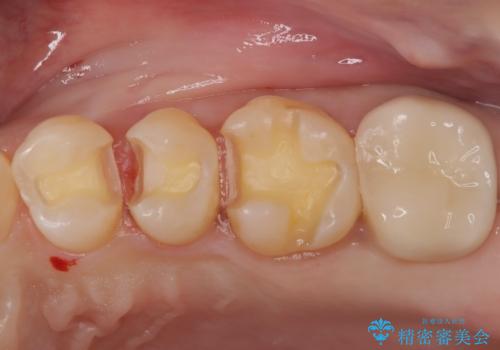

- 他院にて以前治療した修復物の下に虫歯を認めたため、オールセラミックにて修復治療を行なっております。